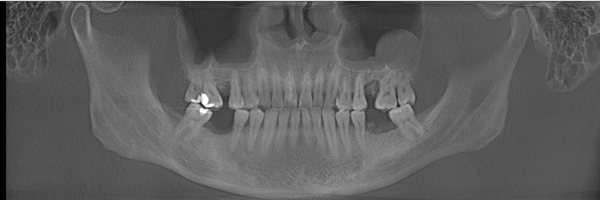

王先生术前牙齿全景片

麦芽口腔医师团队对王先生的口腔ct片进行专业深度的分析之后,决定为其种植麦芽MAC数字化精确种植牙,"麦芽MAC数字化精确种植牙",在保证口腔功能重建和舒适修复的同时,兼顾口腔美学修复,既能快速修复牙齿,恢复咀嚼,同时能够达到较好的美观程度,术中采用STA美国无痛麻醉,确保了手术全程的舒适度,且采用数字化3D种植导板技术,能够更加精确、更加快速找到最佳植入位置,有效避免手术过程遭受痛苦,保证了手术成功率。

王先生术后牙齿全景片